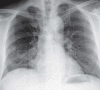

Results: Hemoptysis can be a sign of many different diseases. Its cause remains unknown in about half of all cases. Its more common recognized causes include infectious and inflammatory airway diseases (25.8%) and cancer (17.4%). Mild hemoptysis is self-limited in 90% of cases; massive hemoptysis carries a worse prognosis. In patients whose life is threatened by massive hemoptysis, adequate oxygenation must be achieved through the administration of oxygen, positioning of the patient with the bleeding side down (if known), and temporary intubation if necessary. A thorough diagnostic evaluation is needed to identify the underlying pathology, site of bleeding, and vascular anatomy, so that the appropriate treatment can be planned. The evaluation should include conventional chest x-rays in two planes, contrastenhanced multislice computerized tomography, and bronchoscopy. Hemostasis can be achieved at bronchoscopically accessible bleeding sites with interventionalbronchoscopic local treatment. Bronchial artery embolization is the first line of treatment for hemorrhage from the pulmonary periphery; it is performed to treat massive or recurrent hemoptysis or as a presurgical measure and provides successful hemostasis in 75-98% of cases. Surgery is indicated if bronchial artery embolization alone is not successful, or for special indications (traumatic or iatrogenic pulmonary/vascular injury, refractory asper gilloma).